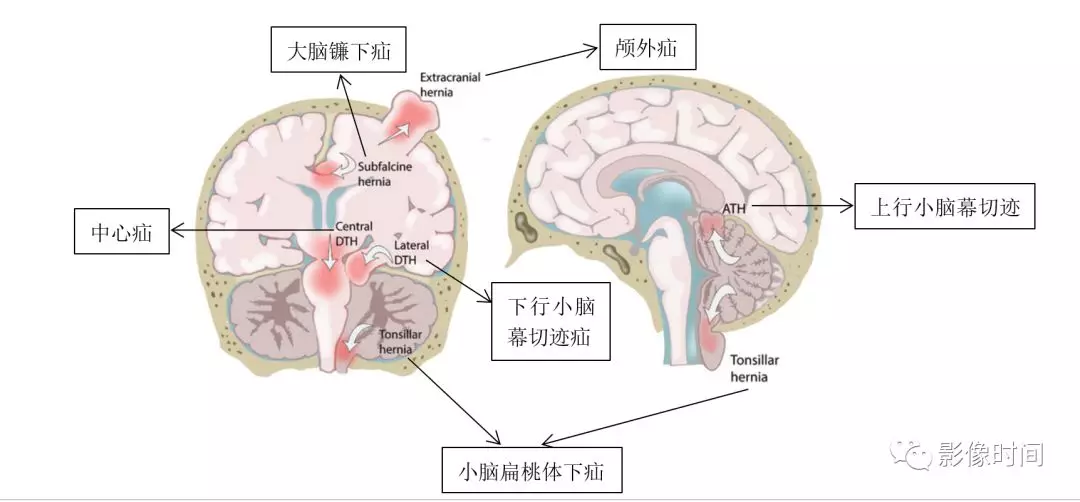

钟书教授专栏丨中枢重症第26期图解脑疝

颅内疝包括:大脑镰下疝,中心疝,海马钩回疝,小脑扁桃体下疝.

血管及脑神经等重要结构受压和移位,被挤入硬脑膜的裂隙或枕骨大孔